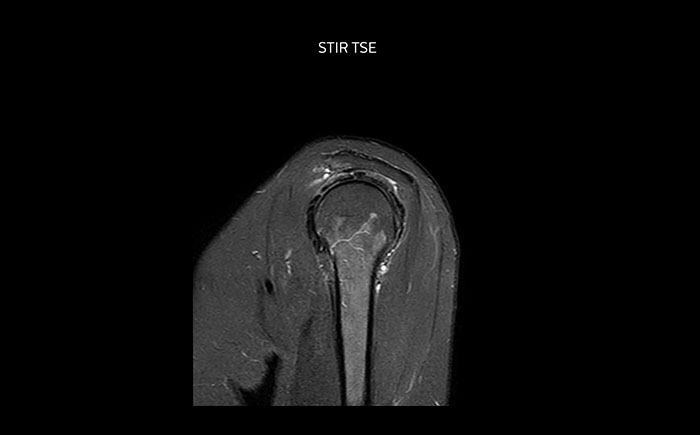

Die Prodiva Schulterspule ist sehr flexibel und hat eine große Abdeckung; dies erleichtert eine gute Positionierung, was wiederum zur ausgezeichneten Bildqualität und hohem SNR beiträgt, die wir in unseren Schulteruntersuchungen erreichen.

Scandauer: 2:55 Minuten, FOV: 160 mm, erfasste Voxel: 0,55 x 0,83 x 3,0 mm.

Scandauer: 04:19 Minuten, FOV: 160 mm, erfasste Voxel: 0,55 x 0,80 x 3,0 mm.

Scandauer: 02:50 Minuten, FOV: 160 mm, erfasste Voxel: 0,70 x 0,99 x 3,0 mm.